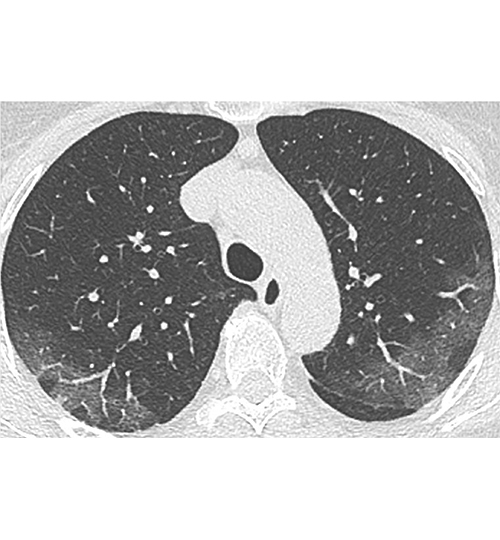

Quelles sont les aspects en TDM ?

Ce sont essentiellement des plages de verre dépoli non systématisées à prédominance sous-pleurale, et à un stade plus tardif de condensation alvéolaire. Il n'y a en règle pas d'excavations, de nodules ni de masses. Les micronodules bronchiolaires, les adénopathies médiastinales et les épanchements pleuraux sont rares, en sachant que ces derniers sont possibles en cas de décompensation cardiaque.

Image : Tomodensitométrie. Patiente de 71 ans sans antécédent, atteinte de Covid-19 et ayant une pneumopathie interstitielle. Aspect typique initial : atteinte bilatérale à type de verre dépoli périphérique sous-pleural. Crédit : Société française de radiologie.